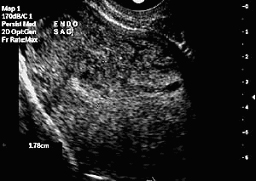

![]() Преди сонохистерография |

![]() След сонохистерография |